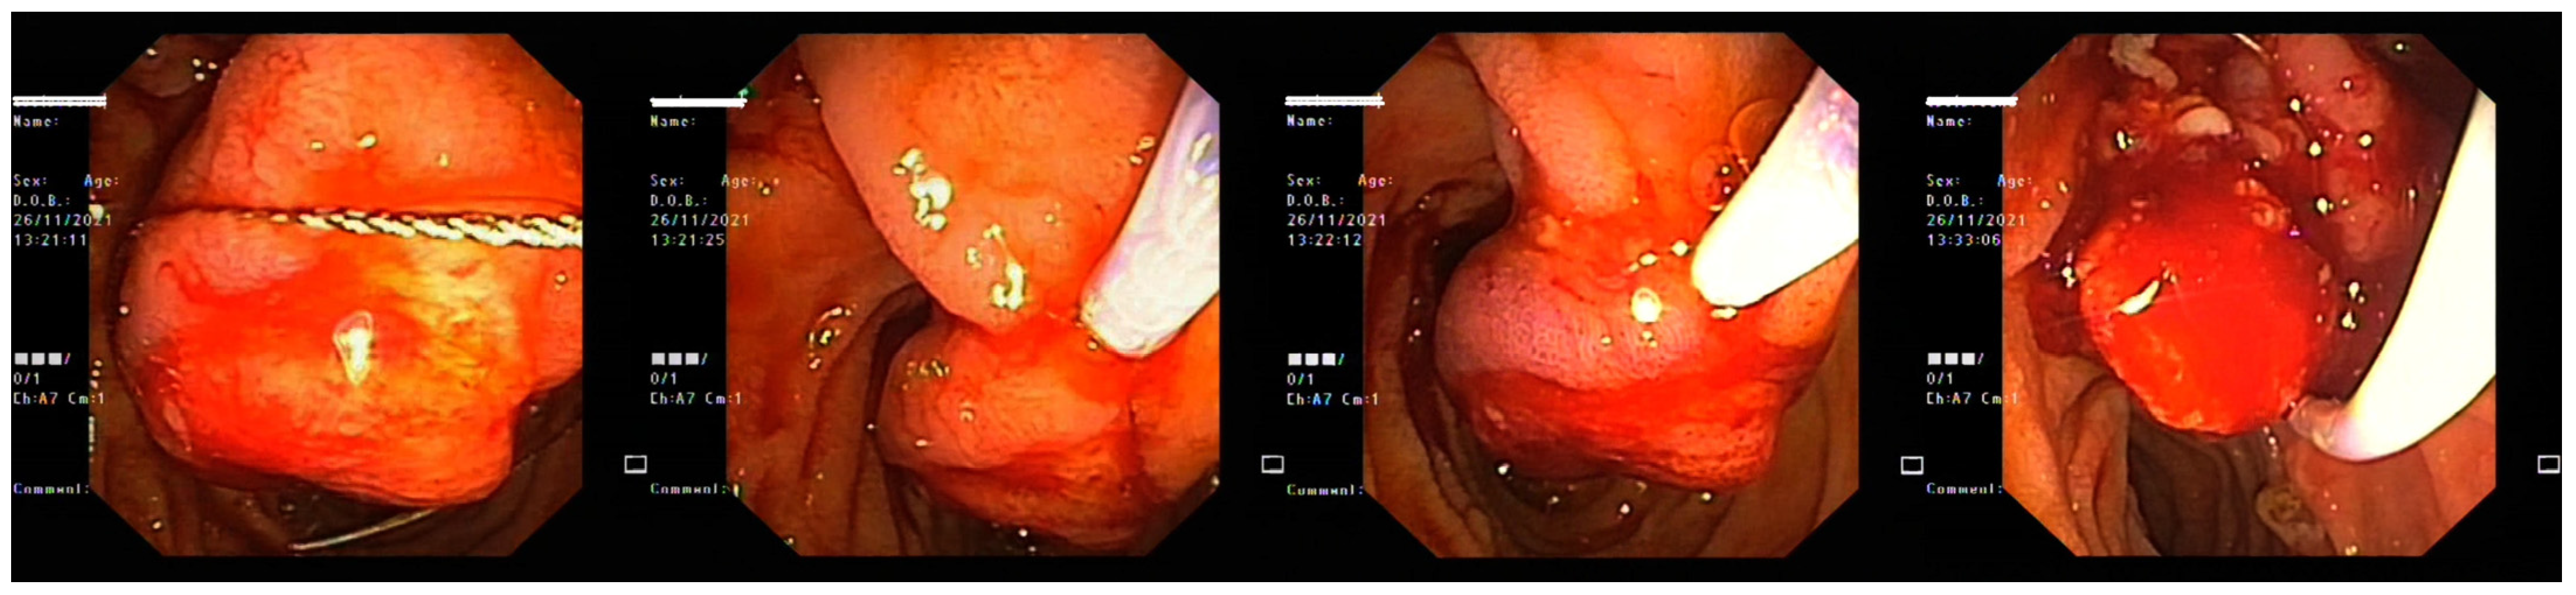

2. Case Report 1

3. Case Report 2

4. Case Report 3